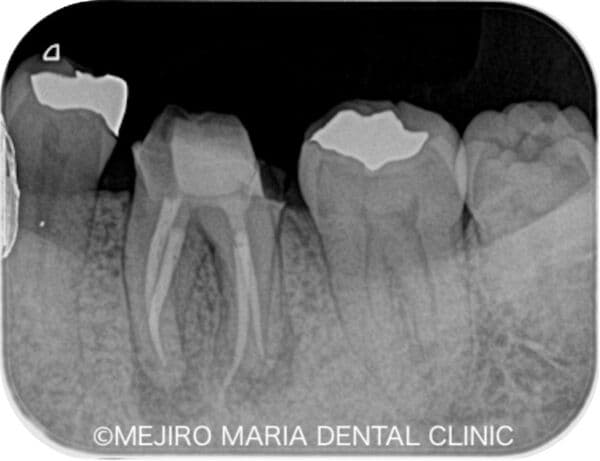

【症例】抜髄(初回根管治療)精密根管治療 ~虫歯治療後に不可逆性歯髄炎に罹患した症例~

治療内容 抜髄(初回根管治療)|精密根管治療

治療期間 2回(経過観察は含まない)

治療回数 精密根管治療2回

治療費用 181,500円(税込 支台築造処置を含む)

リスク・副作用

• 治療計画は口腔内、歯牙の状況により変更する場合があります。

• 精密根管治療は全て自費治療になります。

• 当院の補綴処置5年間の保証は3ヶ月〜6ヶ月の定期的なメインテナンス、定期検診に来院されていない場合は適応されません。

• 根管治療に予後不良が確認された場合は、歯根端切除術を行う必要があります。